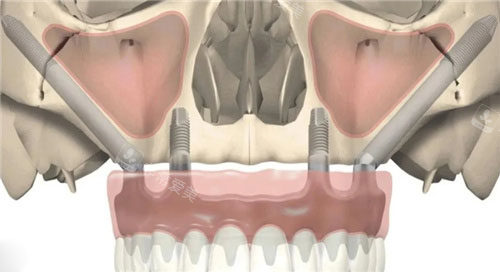

森朗口腔特别擅长穿颧穿翼种植技术,这是针对骨量重的不足患者的解决方案。

传统种植需要先植骨,等待6个月才能种植,而穿颧穿翼技术可以直接植入,大大缩短治疗周期!

穿颧穿翼技术动画示意图

穿颧穿翼种植牙示意图